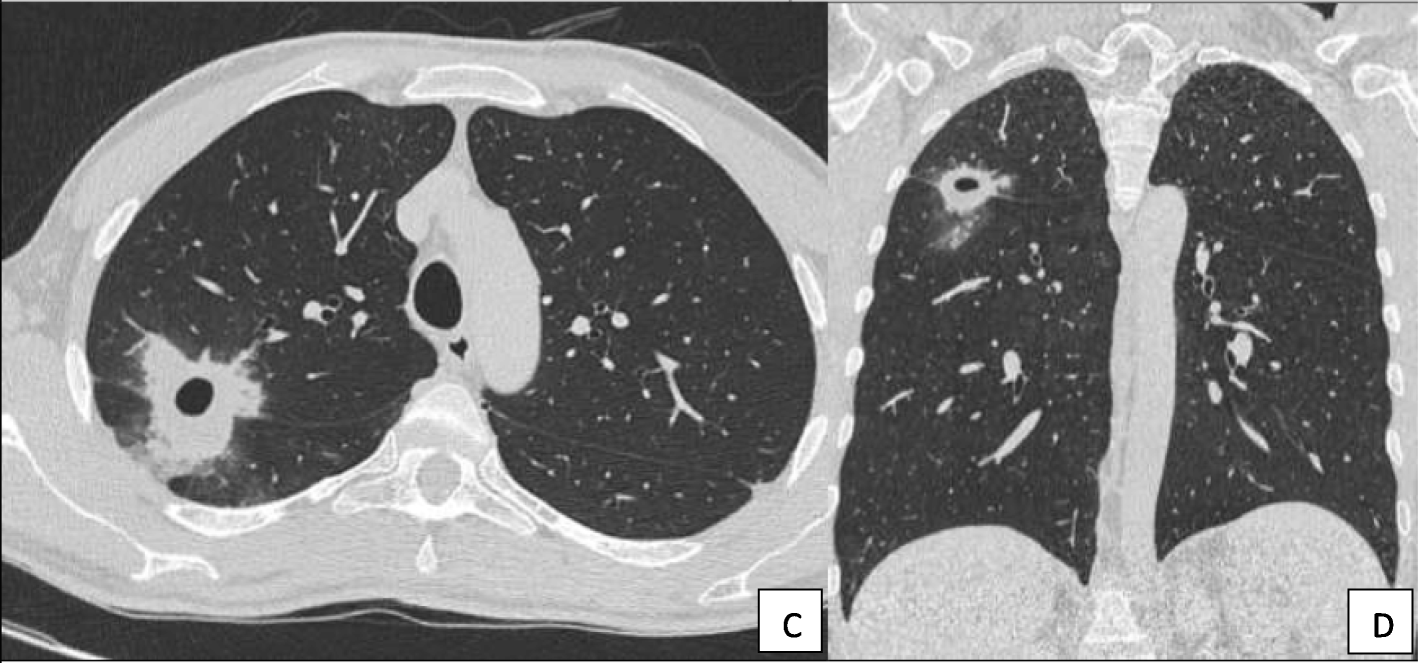

Fig. 2From: Severe pneumonia with formation of a pulmonary cavity associated with long-term rituximab therapy in multiple sclerosisInvolvement of the right upper and inferior lung lobe shown in chest CT in transverse (c) and coronal view (d)Back to article page